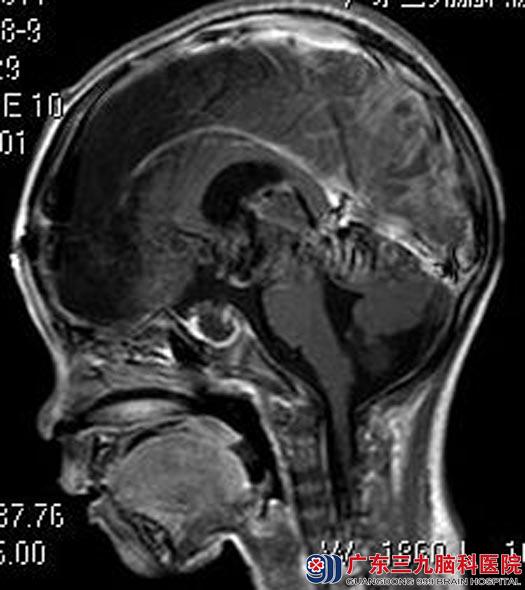

住院在综合神经外科,头颅MR检查提示:鞍区(鞍上为主)示一团块状异常信号影,大小约42.6mm×33.2mm×52.7mm,考虑颅咽管瘤可能性大;左侧大脑半球、左侧基底节区、右侧丘脑及胼胝体多发病变,考虑脑梗塞可能。

由鲁明主任主刀,在全麻下行经前纵裂终板入路鞍区肿瘤切除术,术中显微镜下见肿瘤位于鞍区及鞍上,部分突入三脑室,肿瘤呈灰白色(其间夹带部分淡黄色成分),质软,血供较丰富,予分块切除,肿瘤起源于垂体柄,肿瘤次全切,下丘脑、垂体柄及重要血管保留完整,手术顺利。术后小丰的意识逐渐好转,两周后,可以在家属的扶行下行走。术后病理结果:颅咽管瘤。